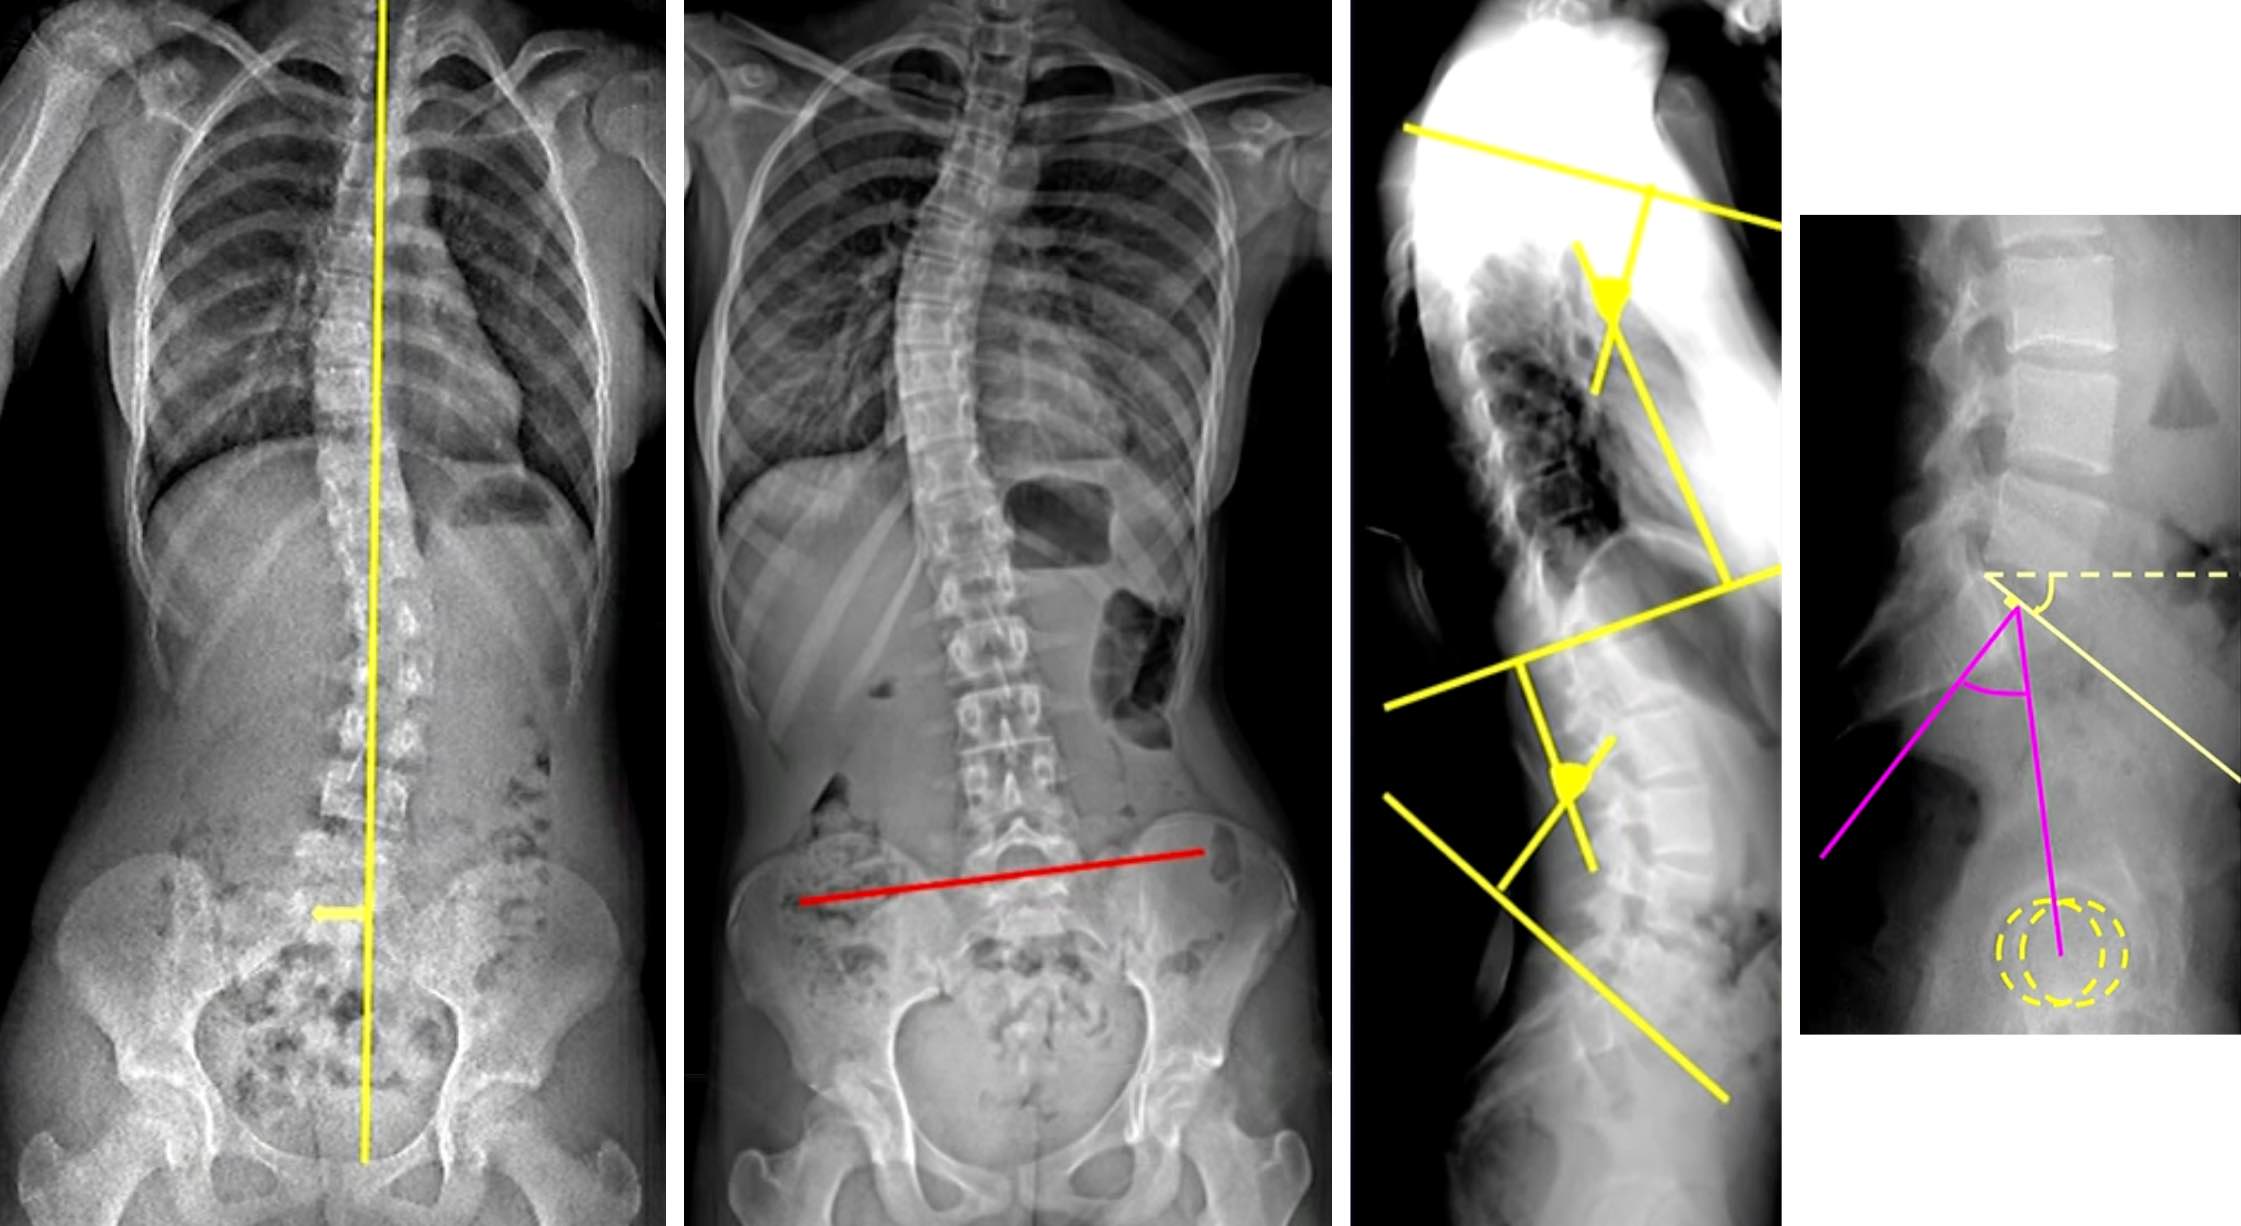

Scoliose mesurant ° entre le plateau supérieur de et le plateau inférieur de .

Stade d'ossification Risser

Bascule du bassin par dénivelation vers la

Absence de malformation ou de lésion vertébrale décelable.

mauvais Pc si > 30°

déséquilibre frontal (fil à plomb électronique centré sur T1)

déséquilibre frontal (fil à plomb électronique centré sur T1)

bascule du bassin (axe du pleateau supérieur de S1)

cyphose thoracique - lordose lombaire (T4 - vertèbre jonctionnelle - S1)

pente sacrée et incidence pelvienne

évolution à la puberté jusqu'à Risser 3

(Risser 1 à 13-14 ans pour les filles et 15-16 ans pour les garçons)